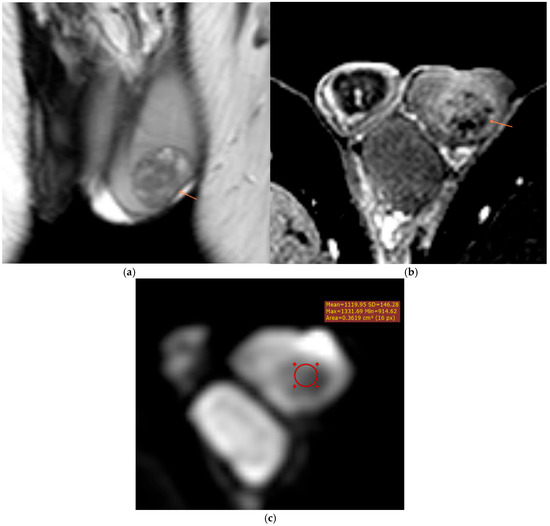

Background: Magnetic resonance imaging (MRI) plays an increasingly important role in the evaluation of scrotal and penile disorders, complementing ultrasonography in cases where findings are equivocal or complex. With its superior soft-tissue contrast, multiplanar capability, and advanced functional sequences, MRI provides unparalleled anatomic and tissue characterization across a wide range of male genital pathologies. Summary: This review summarizes current clinical applications of MRI in scrotal and penile imaging and discusses its diagnostic value, protocol optimization, and interpretive features. In scrotal pathology, MRI accurately differentiates torsion, trauma, infection, and neoplasms, aiding in the distinction between benign and malignant testicular lesions and supporting testis-sparing management. Quantitative diffusion and perfusion metrics further refine lesion characterization. In andrology, MRI biomarkers such as apparent diffusion coefficient (ADC), magnetization transfer ratio (MTR), and proton spectroscopy serve as promising non-invasive indicators of spermatogenic activity in male infertility. In penile imaging, MRI enables precise local staging of carcinoma, assessment of plaque morphology and activity in Peyronie’s disease, evaluation of tissue viability in priapism, and detection of prosthesis-related complications. Conclusions: MRI has become an essential problem-solving tool in the assessment of scrotal and penile diseases, enhancing diagnostic confidence and surgical planning. Future directions include protocol standardization, quantitative parameter validation, and the integration of radiomics and artificial intelligence to improve reproducibility and clinical impact. Full article